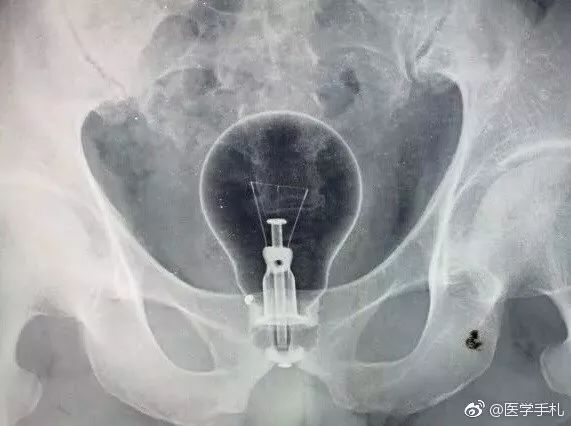

近日,一条求助微博在网络上热传,

一名急诊科医生接诊一位患者,

拍完X光真是吓一跳,

先来感受一下......

这这这...是个灯泡???

没错,确实是灯泡,

但是位置有些尴尬,

另外一位医生,结直肠肛门外科二区罗双灵博士则表示,根据临床经验,塑料类或玻璃类物体表面光滑,且在涂满石蜡油的情况下很难固定。上述微博中提到的灯泡,不仅表面光滑,而且上宽下窄,最宽处直径约8cm,经肛门拖出的可能性很小,强行经肛门拖出不仅容易造成灯泡破裂,而且极易损伤肛门周围组织。